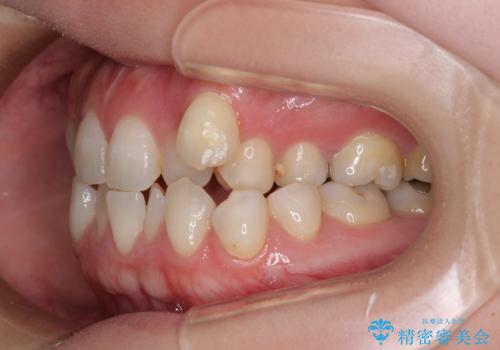

- 左上の八重歯と前歯のデコボコを気にして来院された患者様です。

下顎が左側にズレており、下顎前歯は1歯欠損していたため、左上小臼歯1本を抜歯し、ワイヤー装置にて矯正治療を行うこととしました。

骨格のズレと歯の欠損があったため、仕上がりの調整に時間がかかると思いましたが、舌突出癖の改善や顎間ゴムの装着をしっかりと行ってくださったので、速やかに治療を終えることができました。